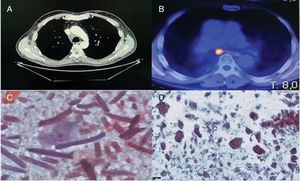

The second case was a 70-year-old man with a history of right lower lobectomy by VATS, with mediastinal lymphadenectomy at 4R and in the subcarinal region (G7) due to a pulmonary nodule measuring 22mm×14mm, with a histologic diagnosis of invasive keratinizing squamous cell carcinoma. In the follow-up CT, enlarged mediastinal nodes were observed, so positron emission tomography (PET/CT) was performed, revealing hypermetabolism at the G7 and right upper paratracheal stations (2R). Nodal neoplastic relapse was suspected, so EBUS-TBNA was performed, showing adenopathy at 2R and a rounded image measuring about 15 mm in its short axis at G7. Three aspirations were made of each lesion in the presence of a cytopathologist, and the initial diagnosis was granuloma. The definitive diagnosis was non-necrotizing giant cell granulomatous reaction and birefringent amorphous material under polarized light, with no neoplastic cells. Similarly, it was confirmed that Surgical® had been used in the adenopathic beds during surgery.